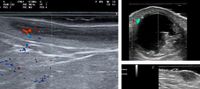

Ecografía cutánea

Ecografía Estética y Dermatológica:

- Detectamos y valorar el estado de los rellenos cutáneos previos del paciente, para evitarle daños en la siguiente infiltración y para conseguir el mejor resultado posible.

- Mapeamos la anatomía de las próximas áreas a tratar, especialmente los vasos sanguíneos, pero también músculos faciales etc.. Así se aplican los tratamientos estéticos con mayor eficacia y sobre todo seguridad.

Galería de imágenes